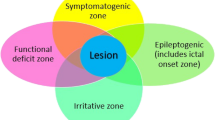

Introduction

Epilepsy surgery is an important therapeutic option, which should be offered whenever possible for patients with pharmacoresistant epilepsy. Comprehensive non-invasive imaging is key to obtaining excellent surgical results. Ictal and interictal scalp electroencephalography (EEG) monitoring and magnetic resonance imaging (MRI) are the most important tools: chances of post-operative seizure control are highest if a lesion is detected, concordant with EEG and seizure semiology, and resected completely [1]. In previous meta-analysis and retrospective studies, the percentage of patients with a good outcome and with MRI-negative epilepsy (MNE) is reported to be as low as 30–50% [1, 2]. Numbers are lowest for patients with MRI-negative extratemporal lobe epilepsy with 38–46% of patients [3,4,5,6] compared to MRI-negative temporal epilepsy, with post-operative seizure control in 55–76% of cases [7,8,9,10,11].

Since it is well-established knowledge that MRI-negative epilepsy is associated with a markedly lower surgical success, there is a certain reluctance to offer surgical therapy (and presurgical evaluation). However, we hypothesize that the outcome in MRI-negative epilepsy is better than reported in most previous studies if supplementary imaging tools are rigorously used together, such as positron-emission-tomography (PET), single-photon emission computed tomography (SPECT), electric source imaging (ESI) based on IEDs in the EEG, and MR-based analysis techniques like morphometric MRI analysis (MAP). Most studies in MRI-negative focal epilepsy investigate the yield of a certain technique, e.g., PET [12, 13] or SISCOM [14, 15], and more recently the yield of multimodal imaging [16]. Here, we present our experience on MRI-negative patients using PET, ESI, MAP and whenever possible SISCOM and determine which technique or combination has the largest impact on post-operative seizure control.